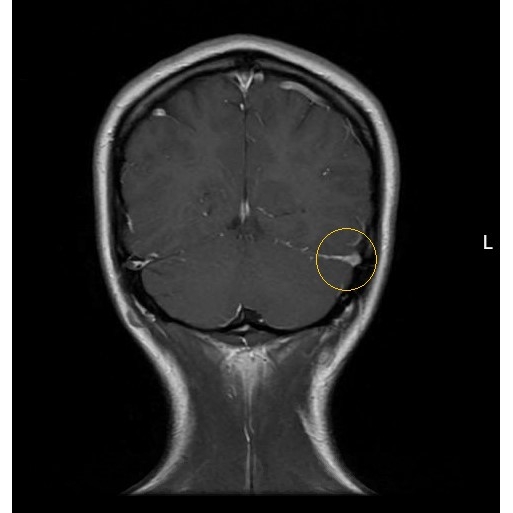

| More Than Just In Your Head: Persistent Headache In A Young Female After Low Impact Head Collision - Page #3 | |||